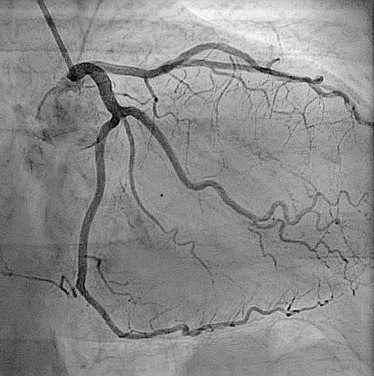

Angiography

A diagnostic imaging process that can help detect narrowing or blockages in blood vessels.